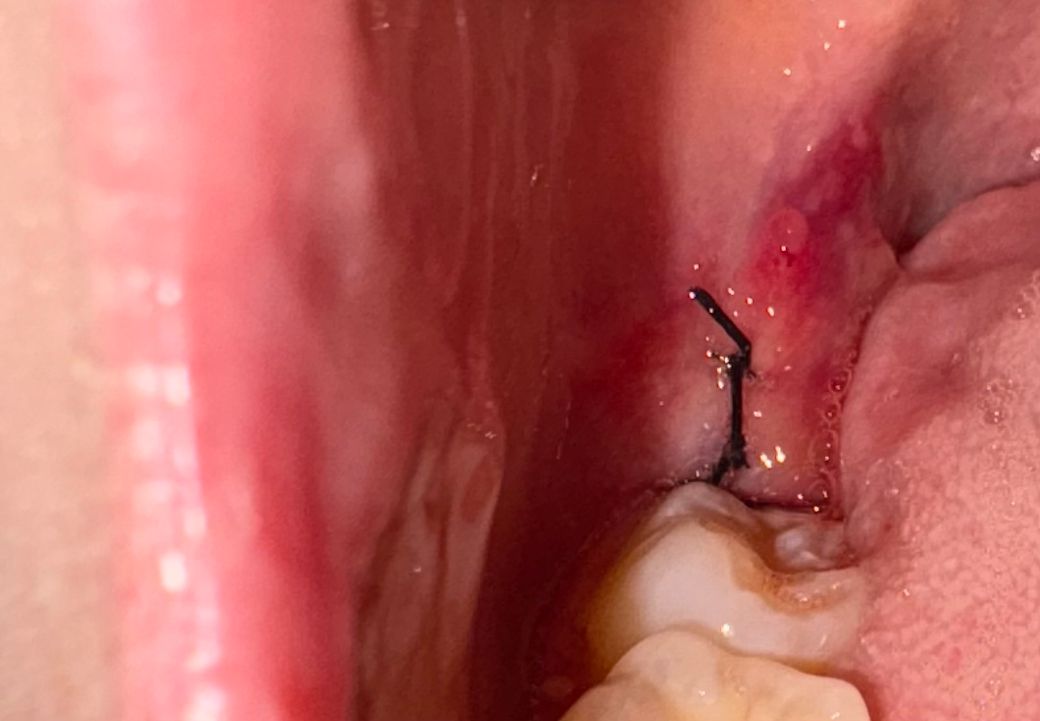

사랑니 발치 후 실밥 뒤에 저게 뭔가요??

사랑니 발치 후에 앞 어금니쪽에 혈병이 생겼는데 혈병이 그런지 자다 일어나니까 없어졌거든요....

오늘 아침에 다시 봐보니까 사랑니 실밥 뒤에 저런 젤리? 같은 것들이 있는데 그냥 부은 건가요 혈병인 건가요??

• 1번 째 사진

발치를 하면서 잇몸이 눌려서 생긴 물집같은겁니다. 크게 걱정은 안하셔도 될것같습니다.

발치 후 발치 부위 단순 염증이 생긴 것 같습니다 양치 등 구강위생관리 잘해주시면 사라질 것 같습니다